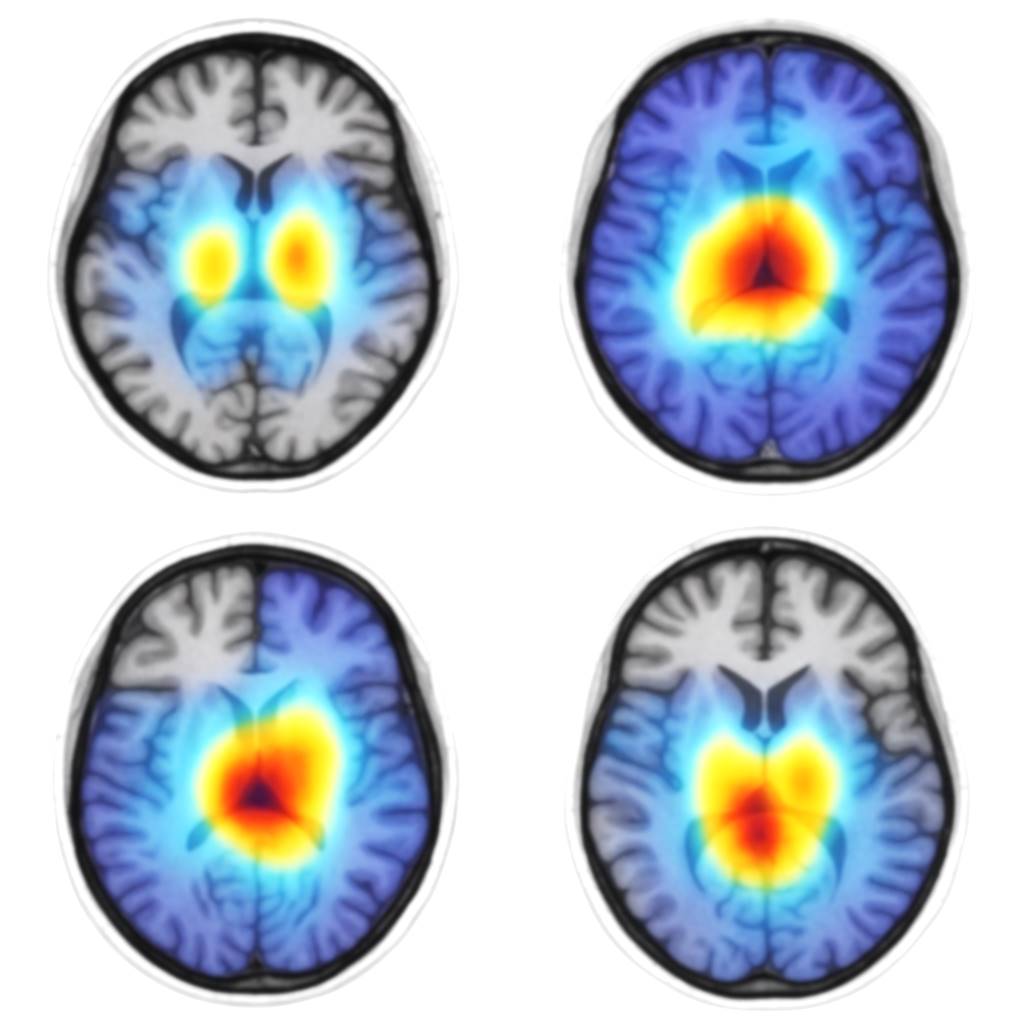

A major advantage of Vision Transformers (ViTs) over traditional convolutional models lies in their capacity for interpretability via multi-head self-attention mechanisms. The figure below showcases actual attention maps derived from ViT layers when classifying MRI scans across different stages of Alzheimer’s Disease (AD).

Figure 17, ViT-derived attention maps overlaid on axial MRI slices. Areas with heightened attention (in red) indicate strong model focus during classification.

The attention heatmaps reveal consistent activation in clinically significant regions of the brain. Notably:

Figure 17. ViT attention maps highlight key brain regions for AD detection.

• Medial Temporal Lobes & Hippocampal Formation: These regions, seen with high-intensity activations (red/yellow areas), are among the first to exhibit neurodegeneration in Alzheimer’s. Their involvement aligns with existing neuropathological evidence emphasizing hippocampal atrophy as an early biomarker of AD progression.

• Posterior Cingulate Cortex (PCC) and Precuneus: The ViT model demonstrates the recurrent focus on these parietal regions, both critical hubs in the default mode network (DMN), often disrupted in early Alzheimer’s pathology.

• Basal Ganglia and Thalamus: Observed in some samples, these areas reflect the model’s sensitivity to subcortical degeneration, particularly in advanced AD cases.

These maps confirm that the ViT model focuses on medically relevant brain regions, leveraging its global attention to detect patterns missed by CNNs boosting both diagnostic accuracy and clinical trust.